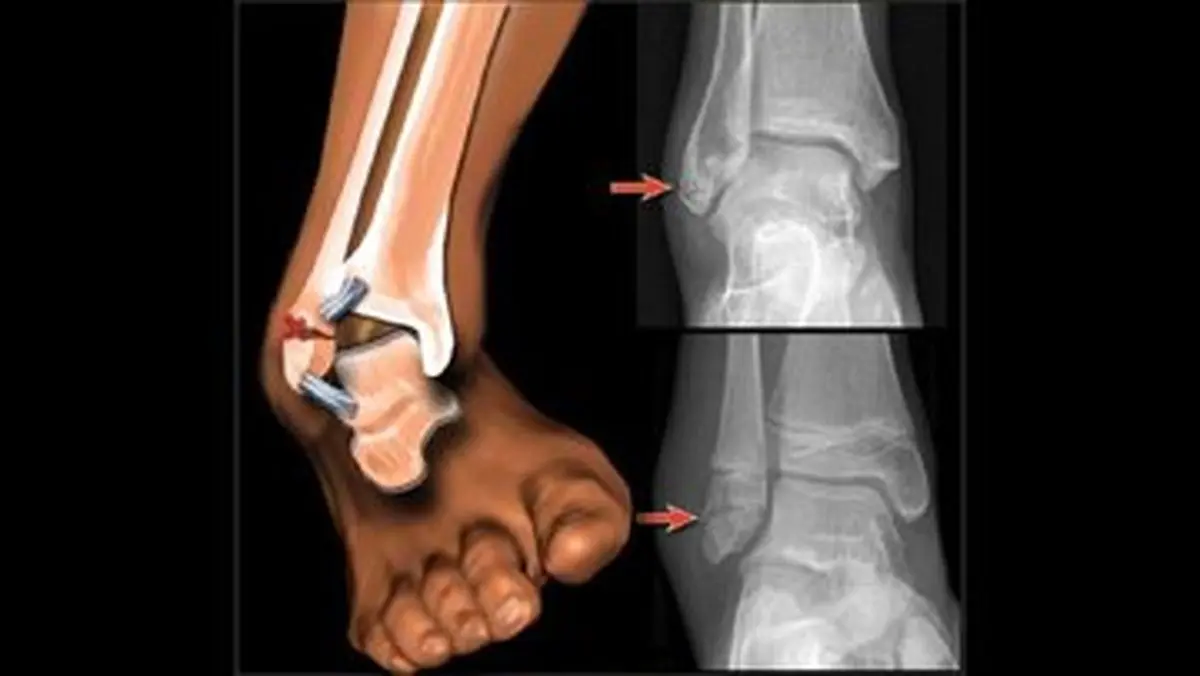

تشخیص شکستگی در صحنههای بحرانی، به دلیل وجود استرس، تاریکی، یا آسیبهای همراه متعدد، میتواند چالشبرانگیز باشد. علائم و نشانههای شکستگی استخوان بسته به ماهیت شکستگی (باز یا بسته، ساده یا مرکب)، میزان نیروی وارده، آستانه تحمل درد فرد مصدوم و وجود آسیبهای همزمان، میتواند متغیر باشد. با این حال، مجموعهای از علائم پایه وجود دارند که مشاهده آنها باید هشداری جدی برای احتمال شکستگی باشد:

۳. تغییر شکل غیرطبیعی عضو: اندام آسیبدیده ممکن است به شکل عجیبی کج، کوتاه یا پیچیده شده باشد و با اندام سالم تفاوت آشکاری پیدا کند.

۴. حرکت نابهجا و غیرطبیعی: در صورتی که شکستگی در محلی غیر از مفاصل رخ داده باشد، ممکن است مشاهده شود که بخشی از اندام در جهتی حرکت میکند که در حالت عادی نباید حرکت کند.

۷. نمایان شدن استخوان: در شکستگیهای باز، سر استخوان شکسته شده ممکن است از سطح پوست خارج شده و دیده شود.